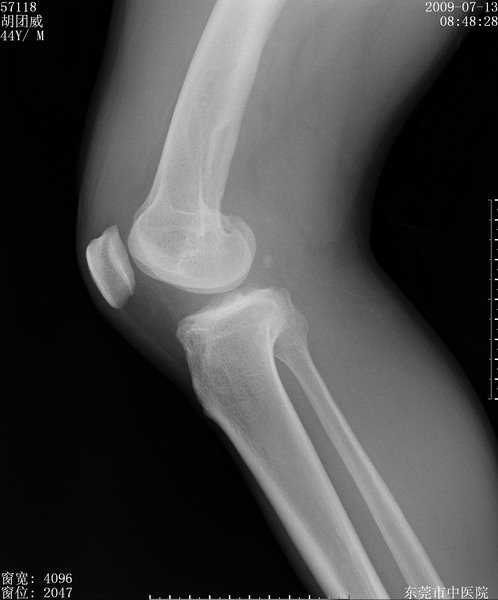

中年男性,膝韧带损伤术前检查!其他病史不清粗,不是我接手病人、且出院了!

1、股骨下段囊状膨胀性病变,边缘硬化明显,内多个残留骨棘呈多房型改变,囊腔密度较高无钙化,膝关节滑膜囊增厚,密度增高,关节腔少量积液。考虑:邻关节囊肿、退变性囊肿(软骨下囊肿)、着色性绒毛结节性滑膜炎、abc、骨巨、良性纤维组织细胞瘤等鉴。虽然年龄偏大,部位于骨端,但有外伤史,本人还是倾向于动脉瘤样骨囊肿(abc)可能性大。邻关节囊肿及软骨下囊肿次之考虑。

2、胫骨髁间棘撕脱骨折,交叉韧带损伤可能;

3、关节退行性改变。

病理结果:色素沉着绒毛结节性滑膜炎

感谢反馈病理结果!本病为慢性关节病变。以关节滑膜高度增生、绒毛结节形成伴含铁血黄素趁着为特点。病因:有炎症、肿瘤、外伤关节出血、代谢障碍、变态反应及感染等学说。增强扫描呈关节腔内单个或多个强化的软组织结节影或滑膜不规则增厚伴关节积液为本病的特征性表现。